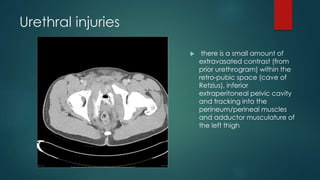

Urethral injuries

 there is a small amount of

extravasated contrast (from

prior urethrogram) within the

retro-pubic space (cave of

Retzius), inferior

extraperitoneal pelvic cavity

and tracking into the

perineum/perineal muscles

and adductor musculature of

the left thigh